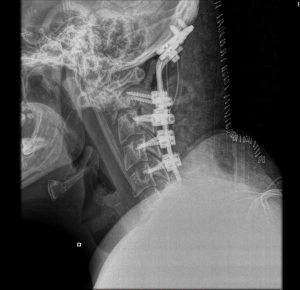

Η μετεγχειρητική πορεία της ασθενούς ήταν ανεπίπλεκτη και ο ασθενής εξήλθε την 3η μετεγχειρητική ημέρα. Η μετεγχειρητική αξονική τομογραφία και ακτινογραφία έδειξε ορθή θέση των μοσχευμάτων και πολύ ικανοποιητική θέση κεφαλής σε σχέση με την ΑΜΣΣ (βλ. εικόνες παρακάτω)

Τα υλικά πρέπει να τοποθετηθούν με απόλυτη ακρίβεια προκειμένω η αυχενική μοίρα του ασθενούς να στηρίξει επαρκώς και σε βάθος χρόνου την κεφαλή. Τοποθετήθηκαν διαυχενικές βίδες (δηλαδή βίδες οι οποίες “πιάνουν” στον αυχένα του σπονδύλου). Η τοποθέτηση των βιδών σε αυτή τη θέση είναι τεχνικά απαιτητική, έχει όμως το πλεονέκτημα ότι προσφέρει τη μέγιστη στήριξη γιατί “πιάνει” σε φλοιώδες οστό (δηλαδή σκληρό οστό) και το μήκος των βιδών μπορεί να είναι πολύ μεγαλύτερο σε σχέση με τις βίδες οι οποίες τοποθετούνται στα πλάγια ογκώματα των αυχενικών σπονδύλων. Συγκεκριμένα, χρησιμοποιήθηκαν βίδες 18-20 χιλ. (έναντι 12 έως 14 χιλ). Αυτό επετεύχθη με τη βοήθεια διεγχειρητικής νευροπλοήγησης (O-arm). Με τον τρόπο αυτό αποφύγαμε μεγαλύτερο μήκος σπονδυλοδεσίας, το οποίο θα ακινητοποιούσε ακόμη περισσότερο τον αυχένα του ασθενούς.

Το τελικό αποτέλεσμα είναι τόσο απεικονιστικά όσο και κλινικά είναι λίαν ικανοποιητικό.